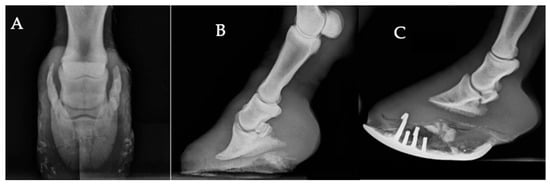

Common Radiographic Findings in Moroccan Working Equids: A Retrospective Study (2015–2022)

Working equids are at high risk of musculoskeletal disorders due to strenuous labor, repetitive tasks, and harsh environmental conditions. This retrospective study describes the distribution of radiographically detected musculoskeletal findings in working equids presented to four Society for the Protection of Animals Abroad (SPANA) centers in Morocco, based on 498 animals and 1125 radiographs collected between 2015 and 2022. The study population was mainly composed of horses (78.1%), followed by donkeys (15.3%) and mules (6.6%). Most were males (65.7%), and the majority were between 5 and 15 years old (60.4%). The distal limb (foot, pastern, and fetlock) was the most frequently examined region (62.7%). Among the animals reviewed, 381 (76.5%) exhibited at least one radiographically detected abnormality, while 117 (23.5%) showed no visible osseous change. The most frequent findings included foot-related changes (36.2%), defined as non-fracture podiatric abnormalities, fractures (29.7%), and periosteal new bone formation (22%). Less frequent findings were degenerative joint disease (8.1%), joint subluxation or luxation (1.6%), epiphyseal abnormalities (1.6%), and angular deformities (0.8%). These results provide an overview of radiographically detected osseous changes in working equids under field conditions. They highlight the diagnostic value of radiography in low-resource environments and provide a basis for future field-based studies. Full article

Figure 1